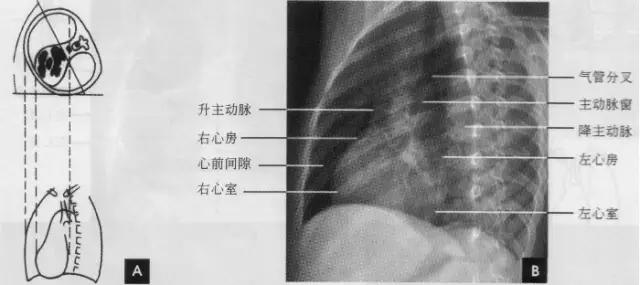

标准右前斜位(又称第一斜位)为后前位向左旋转约45。所得影像。心前缘自上而下由主动脉弓曼升主动脉、肺动脉、右心室漏斗部、右心室前壁和左心室下端构成。升主动脉前缘平直,弓部则在上方弯向后行;肺动脉段和漏斗部稍为隆起;心尖以上大部分为右心室构成。心前缘与胸壁之间有尖向下的三角形透明区称为心前间隙。心后缘上段为左心房,下段为右心房,两者无清楚分界。心后缘与脊柱之间透明区称心后间隙,食管在心后间隙通过,钡剂充盈时显影。右前斜位主要观察右室流出道及左心房大小(如下图)。